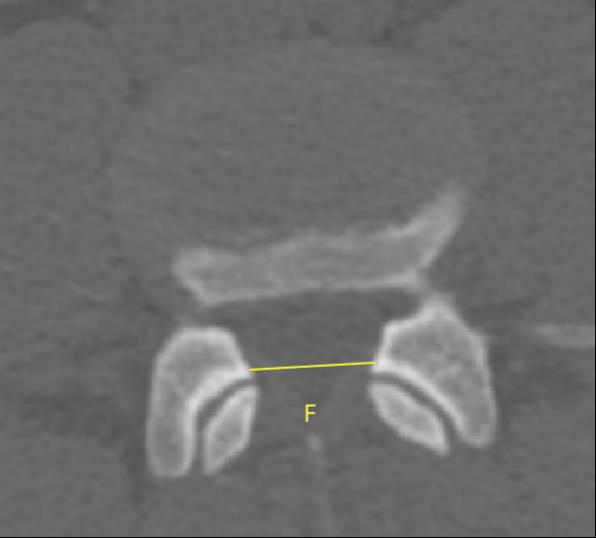

2、通过术前CT测量L4-5节段手术部位的(1)上位椎体后下角水平方向到关节突关节的距离(A);(2纤维环后缘的中点水平方向到关节突关节的距离(B);(3下位椎体后上角水平到关节突的距离C);(4上位椎体的椎弓下切迹与下位椎体椎弓上切迹连线的距离D), 6;(5)在手术节段的棘突矢状位CT层测量椎间隙高度(E), 7;(6)在手术节段的关节突关节横截面CT层测量关节突间距离(F), 8,再通过术中及术后CT判断患者椎间孔成型级别,将A-F测量数据与5级成型中的各级别成型进行相关性分析。

8  F的测量方式

3、通过术前术后VAS评分、ODI评分及MacNab评定进行5级成型技术的疗效分析。